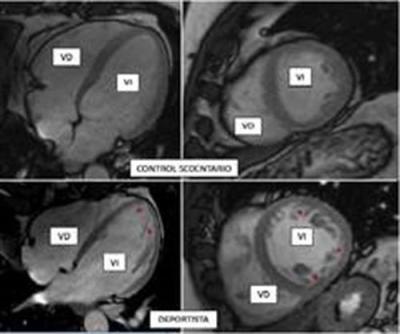

La práctica de ejercicio, intenso o moderado, es una de las recomendaciones de salud aceptadas por todos los expertos. Sin embargo, el entrenamiento de alta intensidad puede desencadenar una serie de cambios fisiológicos en el organismo, incluyendo el corazón. Por ejemplo, se sabe que los deportistas presentan una adaptación de su corazón al entrenamiento que, entre otros fenómenos, puede incluir un aumento de las trabéculas en su interior ("hipertrabeculación"), que es benigna pero que puede confundirse con una patología genética hereditaria, la miocardiopatía no compactada, que puede causar muerte súbita.

En la miocardiopatía no compactada, las paredes del corazón se adelgazan y el músculo cardiaco, habitualmente compacto, se sustituye por una porción esponjosa (trabeculada), que se comunica directamente con el interior de los ventrículos.

El problema es que esta enfermedad se identifica, en muchos casos, en personas jóvenes asintomáticas antes de que aparezcan síntomas y, en esos casos, "una de las recomendaciones es interrumpir inmediatamente la actividad física ya que puede causar la muerte súbita", apunta este cardiólogo del CNIC. Sin embargo, la presencia de trabéculas no siempre va ligada a la miocardiopatía no compactada; así, asegura el doctor Ibáñez, "se ha observado que, ante diferentes condiciones fisiológicas, como el entrenamiento de alta intensidad o el embarazo, puede observarse un cambio en la morfología del corazón que es similar en estructura a la de la miocardiopatía no compactada".

El trabajo ha evaluado mediante resonancia magnética cardiaca la presencia de criterios reconocidos de miocardiopatía no compactada en más de 700 participantes del estudio 'PESA-CNIC-SANTANDER', trabajadores sanos del Banco de Santander que realizan diferentes grados de actividad física, pero que no practican deporte de forma profesional.

Lo primero que se observó es que el músculo cardiaco de los participantes, que de forma persistente realizaron una actividad física vigorosa a lo largo de este periodo de tiempo, se adaptaba al ejercicio aumentando su volumen y su masa muscular. "Estos cambios son conocidos como 'corazón de atleta', y se consideran fisiológicos", explica García-Lunar.

Un hallazgo más novedoso fue que una tercera parte de los individuos (hombres y mujeres) con un nivel elevado de actividad física vigorosa habitual cumplía además los criterios diagnósticos de miocardiopatía no compactada, pero, obviamente, no estaban enfermos.